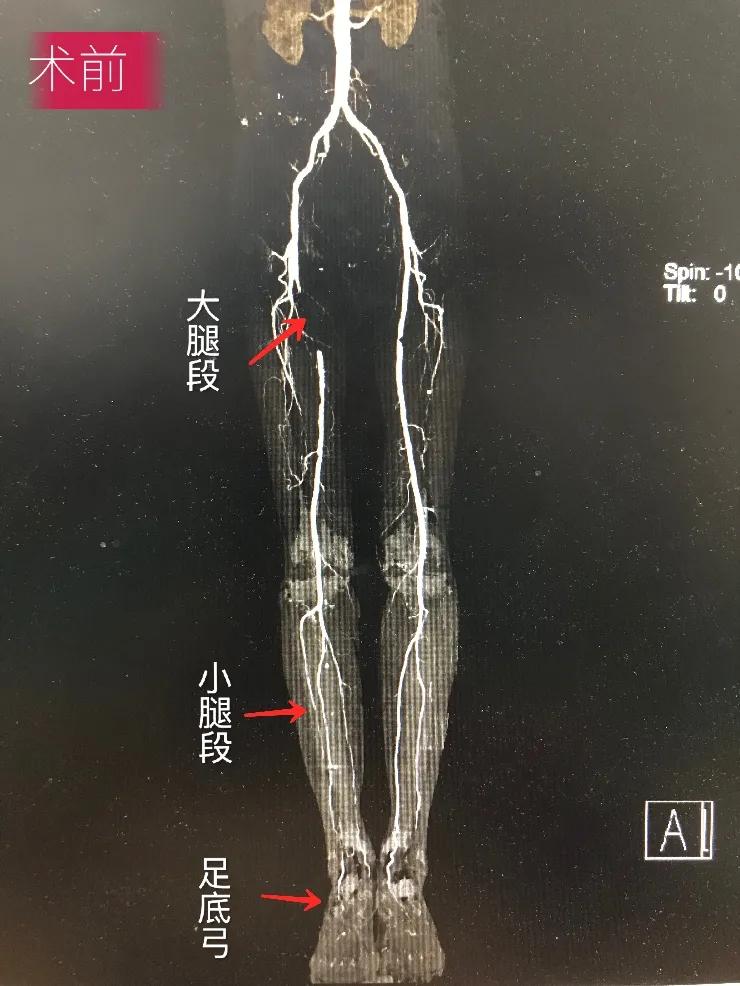

术前 闽东医院供图

家住寿宁县79岁老沈就是得益于该项技术的患者之一。老沈长期存在间歇性跛行、静息痛等症状,严重影响睡眠及生活质量,既往有长期吸烟史以及高血压、高血脂基础疾病。5月20日,患者及其家属慕名到闽东医院介入医学科,陈铃雄接诊后,详细询问病史、进行专科查体及影像读片等综合评估后,经征得患者及其家属同意,5月25日,在局部麻醉及DSA下为患者行“右下肢动脉造影+成形+支架置入术”,术后造影右下肢动脉血流恢复,患者感觉右下肢疼痛明显好转,夜间酣然入睡,次日查房向陈铃雄及其团队表示感谢。5月29日,患者治愈出院。